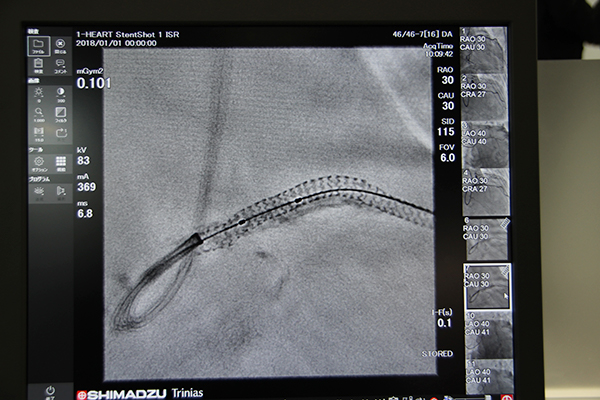

●血管撮影装置:“可視化”で手技を支援する「Trinias」シリーズ「unity edition」

2017年10月に国内販売を開始した血管撮影システムTriniasシリーズunity editionは,新しい画像処理技術やチルト機能を備えたカテーテルテーブルの組み合わせなどにより,高度なインターベンションを強力に支援するシステムである。会場には,下肢撮影など広範囲の撮影にも対応する16インチ×12インチの大視野FPDを搭載した「Trinias C16 unity edition」を,新しいカテーテルテーブルと組み合わせて展示した。

島津は画像処理技術の開発において,“可視化”に重点を置いている。術中にステントの形状やポジショニングをリアルタイムに確認するためのアプリケーションが,“SCORE StentShot”と“SCORE StentView”である。SCORE StentShotは,従来と照射線量を変えずにノイズを約50%低減することができ,拡張したステントの編み目構造も明瞭に視認できる。また,SCORE StentViewは心拍により動くステントを固定・強調表示し,これらにより経験の浅い術者にもわかりやすい画像を提供する。

DSAを支援する“Flex-APS”(Flexible Active Pixel Shift)は,体動による造影前後の位置ズレを,ピクセル単位で三次元的に自動補正する機能で,アーチファクトのない精度の高いDSA画像を提供する。

また,高齢化に伴い増加傾向にあるPAD(Peripheral Arterial Disease:末梢動脈疾患)の診断に有用な機能として“SCORE Chase”をアピールした。従来,下肢造影画像は分割して撮影し,つなぎ合わせる必要があったが,SCORE Chaseでは造影の様子をリアルタイムに確認しながらテーブルを動かして連続的に画像を収集し,撮影終了後に自動で長尺画像が生成される。造影,撮影が1回ですむため,従来と比べ造影剤量・被ばく線量を低減することができ,低侵襲な検査を提供する。

ステントの編み目構造も視認可能にする“SCORE StentShot”